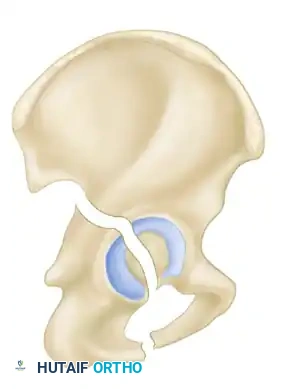

The Letournel and Judet classification system remains the universally accepted framework for categorizing acetabular fractures. It is predicated on the concept of the acetabulum being supported by an inverted "Y" consisting of an anterior column and a posterior column. The system divides fractures into two broad categories: Simple Fracture Types and Associated Fracture Types.

Simple fractures involve a single primary fracture line or isolate a single anatomical region of the acetabulum. There are five simple patterns:

- Posterior Wall Fractures: The most common acetabular fracture, frequently associated with posterior hip dislocations. The fracture involves the posterior articular surface, compromising hip stability.

- Posterior Column Fractures: The fracture line begins at the greater sciatic notch, traverses the articular surface, and exits through the obturator ring (ischio-pubic ramus), detaching the entire posterior column.

- Anterior Wall Fractures: Rare injuries involving the anterior articular surface, typically exiting through the anterior border of the ilium.

- Anterior Column Fractures: The fracture line originates anywhere along the anterior border of the ilium (from the iliac crest to the anterior inferior iliac spine) and exits through the superior pubic ramus.

- Transverse Fractures: A single fracture line crosses both the anterior and posterior columns horizontally, dividing the innominate bone into a superior (iliac) segment and an inferior (ischiopubic) segment.